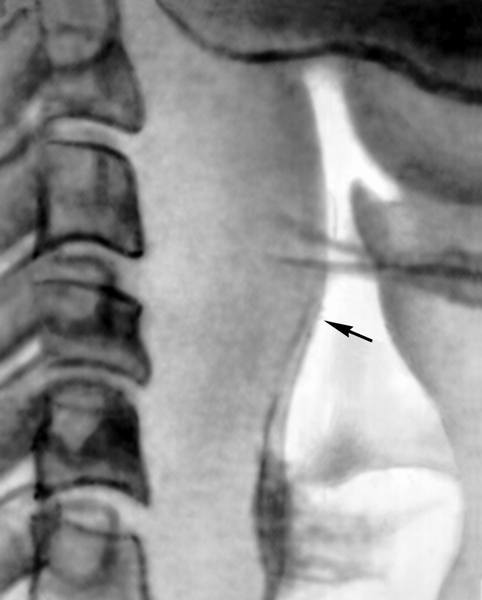

Заглоточный абсцесс диагностируется отоларингологом на основании данных, полученных в ходе осмотра пациента и проведения фарингоскопии. При осмотре обращает на себя внимание вынужденное положение головы пациента, локальный отек в области шеи, увеличение лимфатических узлов и их болезненность при пальпации. Фарингоскопия выявляет локальную инфильтрацию на задней стенке глотки и опухолевидную припухлость шаровидной формы. Пальцевое исследование глотки определяет болезненность в месте припухлости и наличие симптома флюктуации, свидетельствующего о том, что образование представляет собой скопление жидкого гноя.

Для выявления сопутствующих заболеваний уха и носоглотки, которые возможно стали причиной формирования заглоточного абсцесса, может потребоваться отоскопия, риноскопия, УЗИ и рентгенография околоносовых пазух, рентгенография позвоночника в шейном отделе.